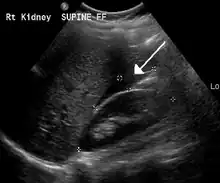

Blood in Morrison's pouch between the liver and kidney due to a ruptured ectopic pregnancy

The most common complication is rupture with internal bleeding which may lead to hypovolemic shock. Death from rupture is the leading cause of death in the first trimester of the pregnancy.[9][10][11]